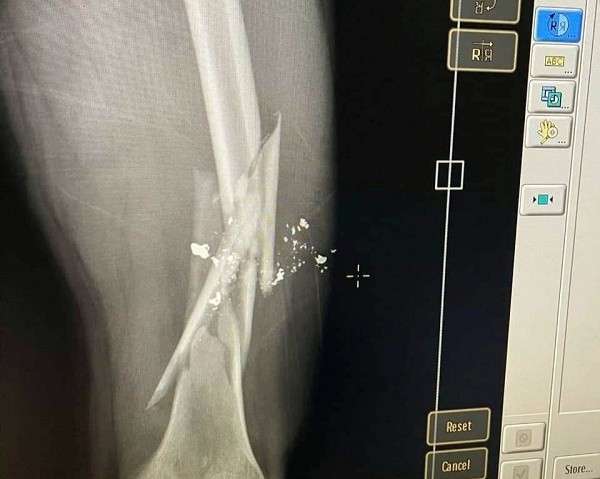

Phim chụp xương đùi bị gãy nát được cho là của nạn nhân.

Sau khi thanh toán xong, cả nhóm ra khỏi quán rồi đứng lại tiếp tục nói chuyện. Do bức xúc vì bị đấm vào miệng khi còn ở trong quán, Hòa đã xách súng bắn anh Giang dẫn đến gãy xương đùi. Nạn nhân sau đó đã được đưa đi bệnh viện cấp cứu.